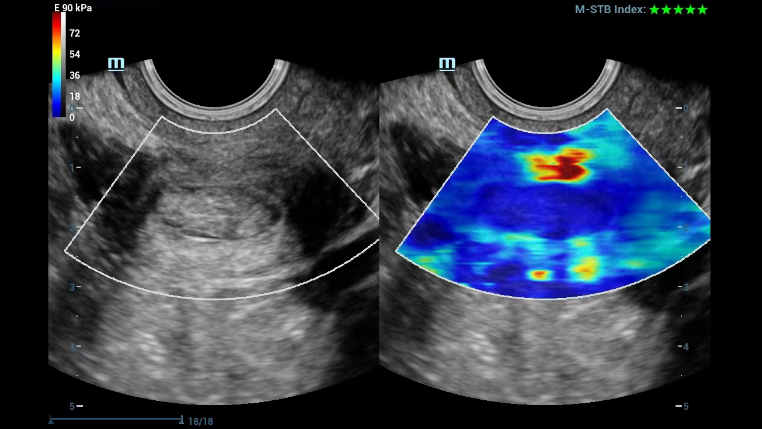

UWN+ CEUS provides excellence contrast agent sensitivity and image penetration to get more diagnosis information for gynecology tumor or other difficult diseases. Also MindrayŌĆÖs STE (Sound Trouch Elastogtaphy) can quantitatively evaluate tissue stiffness which is helpful for previse diagnosis of difficult uterus, cervix and ovary diseases.